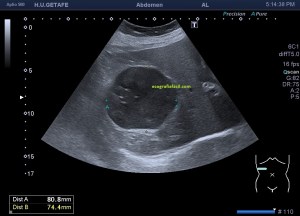

En la imagen 3 ves una imagen de un lipoma, mide 7 cms, la huella de la sonda mide 5cms, la «panoramic view» posee una regla centimetrada que sigue el contorno de la imagen, justo en la profundidad de la misma y lo marca la flecha amarilla. La profundidad la marca la flecha roja y la flecha blanca marca el rango centimetral de los 5cms, fíjate que la línea blanca es ligeramente mayor cada 5 cms. Sirve de referencia, como en la imagen 4 donde ves una colección en el glúteo de más de 10 cms.

Podemos medir valores superiores a los 15cms con alta calidad de imagen…podemos llegar a medir valores por encima de los 25 cms…es verdad que no todos los equipos tienen este ajuste ecográfico, es decir, es una aplicación y por tanto hay que pagarla.